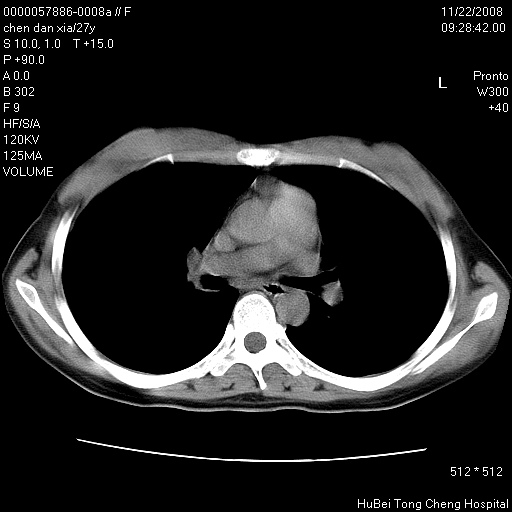

标题: CT16752:F,27Y。发热咳嗽20余天,伴盗汗。 [打印本页]

标题: CT16752:F,27Y。发热咳嗽20余天,伴盗汗。

右下肺见片絮状影,两肺野内分布不均的小结节影,结核并肺内播散可能性大,建议结合实验室检查 .

右下肺纹理模糊;纵隔可见肿大淋巴节;右心缘旁结节,边缘光滑,纵隔窗病变范围较肺窗明显小,首先考虑右下肺结核,不排外淋巴瘤

双肺纹影普多,部分呈网状,支炎或淋巴管炎?

纵隔内淋结肿

局部胸膜增厚

似有粟米状结节。考虑粟粒型肺结核?